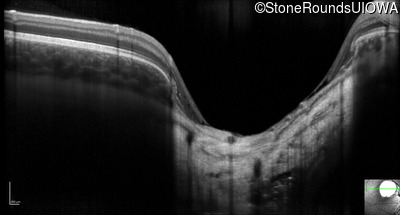

Optical Coherence Tomography - Left - 20/50

Exemplar / OCT Stack

OCT Stack